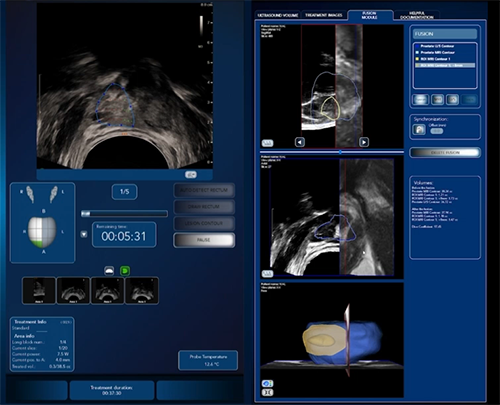

新一代海扶刀結合MRI核磁共振和即時超音波影像,提供多元的客製化治療方案精準局部摧毀癌細胞

圖片來源:徐易廷醫師提供